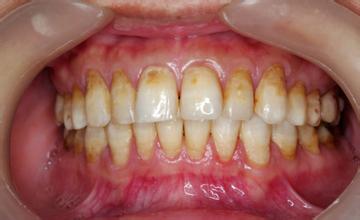

氟斑牙是一种常见的口腔疾病,往往会导致牙齿变色发黄,严重影响一个人的形象,给人们的生活带来一定影响,因此一定要及时治疗。那么氟斑牙该如何治疗呢?

广州越秀圣贝口腔门诊部表示:氟斑牙有多种治疗方法,如炫彩美白、美容冠等,但具体需要根据患者的病情程度决定:>>>预约牙管家更清楚家

轻中度氟斑牙的治疗方法

炫彩美白:炫彩美白是目前先进的牙美白,可以深层美白牙齿,效果良好。操作过程需三十分钟左右,操作过程舒适,护理得当可达5年。>>>炫彩美白真的好吗?点击预约牙管家

重度氟斑牙的治疗方法

圣贝微贴面:亲贝微贴面经先进烧结而成,更胜传统瓷贴面,是较佳的一体化预制瓷块。微贴面制作工艺精细,让修复的牙齿与真牙无异,疗程快捷方便,使用寿命长达几十年,是美白氟斑牙的好方法。【阅读:广州治疗氟斑牙哪里好?】

圣贝美容冠:圣贝美容冠是源自的牙齿修复美白,其性能更佳强大,优于烤瓷牙和传统美容冠,可与天然牙齿媲美,对人无害,是美白氟斑牙的良好方式。并且其原材料均系国外引进,全国联保,提供终生维护。>>>治疗氟斑牙的费用是多少?点击预约牙管家